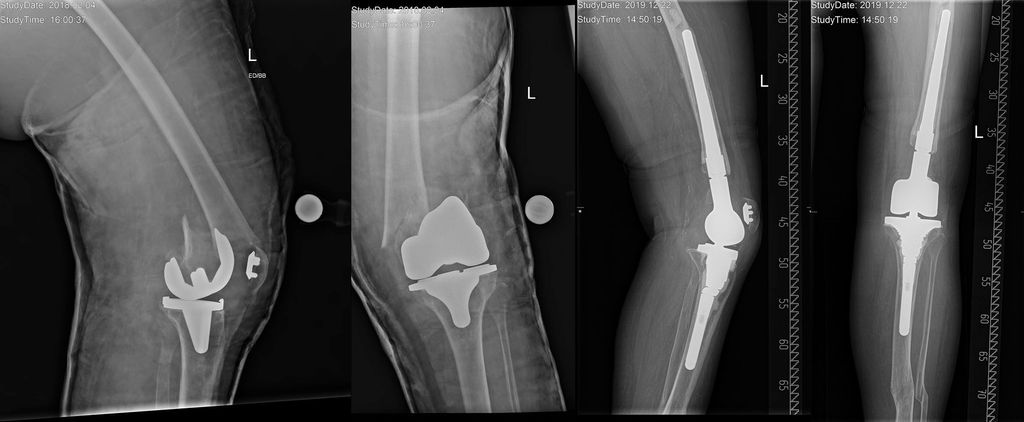

Abb. 2: Periprothetische Femurfraktur vom Typ III nach Su et al. Die Autoren versorgten diese Fraktur mittels distalen Femurersatzes und kompletten Systemwechsels